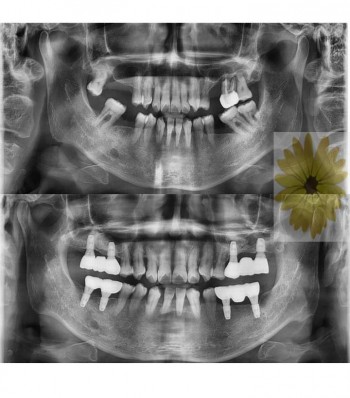

민들레치과 치료 전후사례